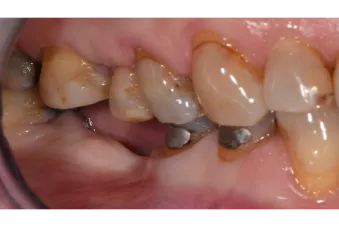

Clinical cases

Interested in how our products perform in real life? Then have a look at our clinical cases, where you can see how our products can change a patient’s life.